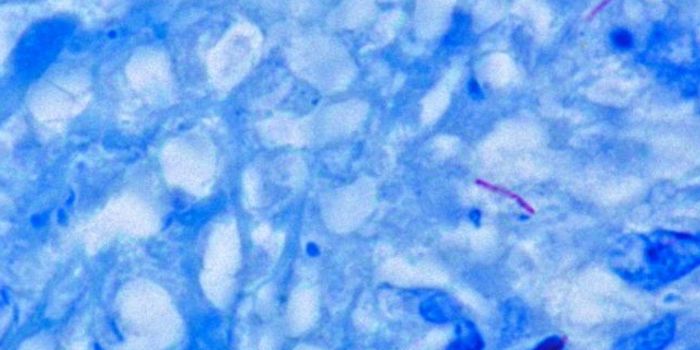

FEB 01, 2021MicrobiologySpirochetes are a type of free-living, spiral-shaped bacteria, some of which are harmless and others that can cause dise ...